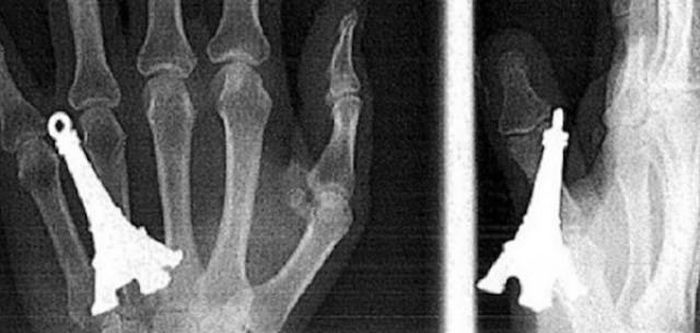

Предметы, которые не очень хочется видеть внутри себя

Под рентгеновскими лучами порой видны не только внутренние органы и кости, но и инородные тела, попавшие в организм

Истории попадания этих предметов в организм могут быть самыми невероятными и запутанными, но больше всего медиков интересует процесс их извлечения, впрочем, в этом заинтересованы и сами пациенты, допустившие нечто подобное со своим телом.